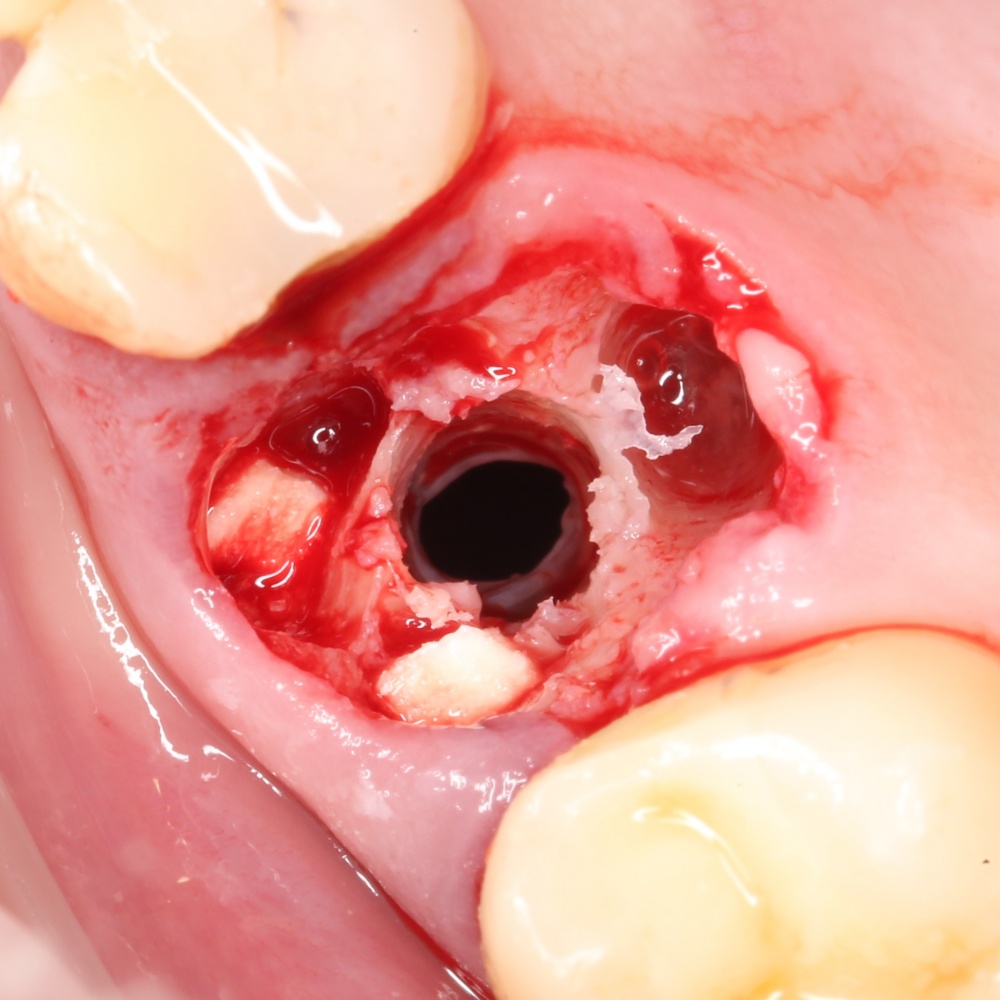

Однако, в этот раз я решил немного изменить план лекции. Теперь свою часть каждого из семинаров я буду посвящать какой-то конкретной операционной методике, рассказывая о ней чуть подробнее, чем принято говорить «бесплатно». И начнём мы с синуслифтинга, самой распространенной остеопластической операции в мире.

О том, почему открытый синуслифтинг безопаснее закрытого. И почему при закрытом синуслифтинге я не рекомендую использовать биоматериалы:

Каковы показания к открытому синуслифтингу? Когда его можно проводить совместно с установкой имплантов. а когда лучше сделать отдельным этапом?

Как правильно и аккуратно сделать доступ в верхнечелюстную полость? И как создать достаточное по объёму субантральное пространство?